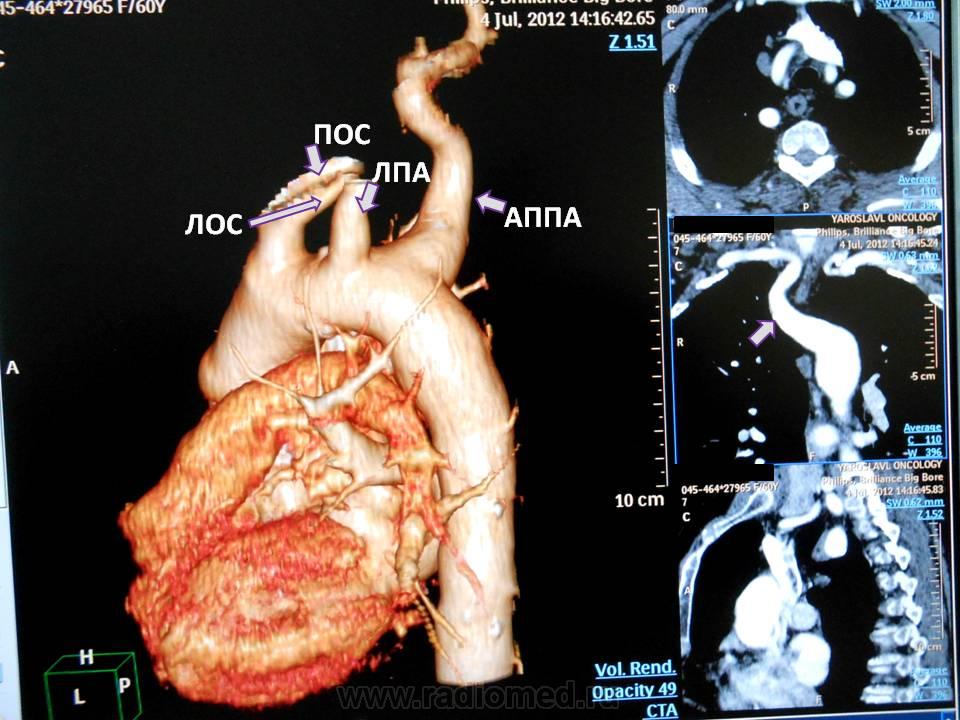

Автор: Бодров Юрий Дмитриевич . Аберрантная правая подключичная артерия